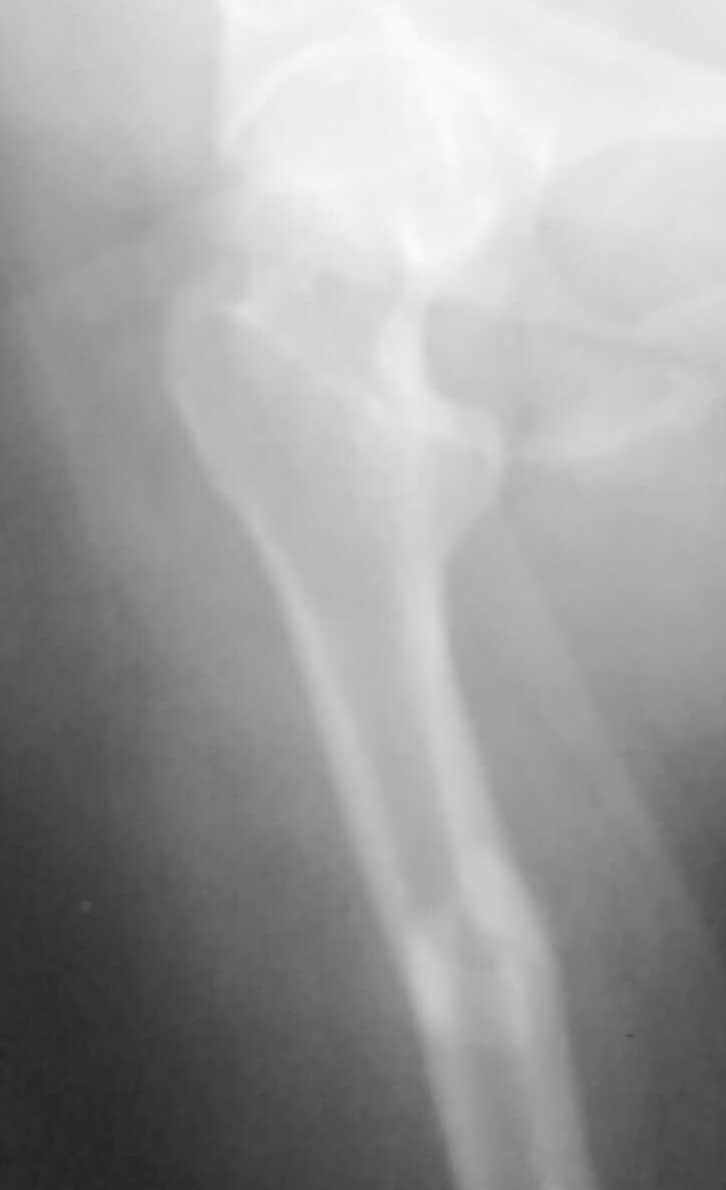

[Ortho] перелом бедренной кости

дополнительные снимки

Имя     : Фото076.jpg